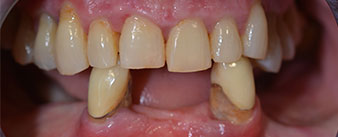

The 64-year-old patient presented with residual dentition of teeth 38, 33 and 43 and a clasp denture in the mandible (Fig. 1 and 2).

residual dentition

Fig. 1

Fig. 2

The necessary periodontal treatment and extraction in the maxilla was to be performed at a later point in time, as the patient is a teacher and was busy with school leaving exams at the time. She could neither eat nor speak properly, as the temporary prosthesis was very fragile, breaking regularly and under the slightest strain.

Following an explanation of the various treatment options open to her, the patient decided on extraction of the residual dentition in the mandible, an immediate implantation and treatment with the Fast & Fixed method (bredent medical), whereby the provisional fixed denture is screwed onto four implants on the same day as the surgery. The goal was to operate on the patient on the Friday so that she could assist in the oral examinations on the following Monday.